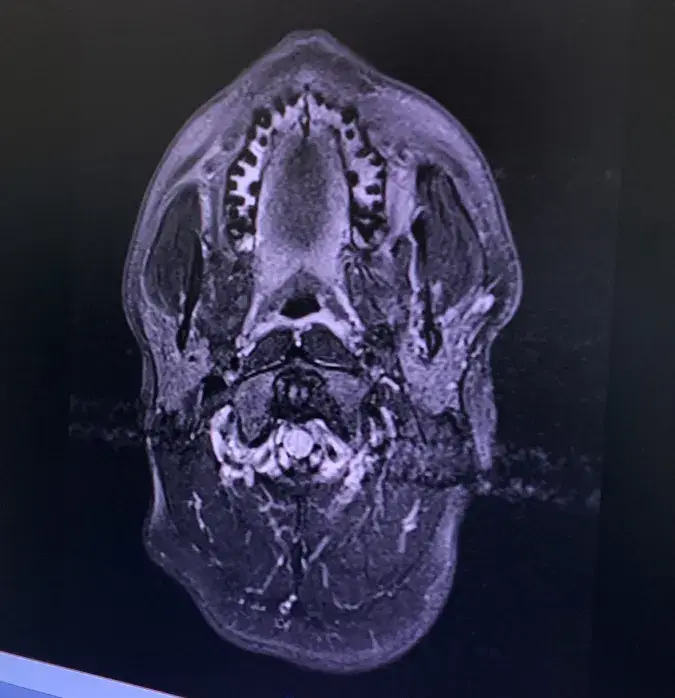

MRI of Mike’s brain show the 3 trauma spots where blood clots traveled through his heart, to his brain.

Several weeks of tests, brain scans and MRIs revealed the cause – Congenital Heart Disease. “A doctor showed me my heart on the scanner. He pointed and said ’You see that there? You’re missing a bit’. It was just a big hole. I had lived for 26 years with a 2 cm Atrial Septal Defect.”